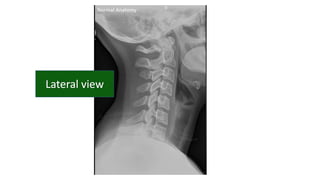

• #22 Flooe of post cranial fossa Angle of mand Ant post arch of atlas Dens of axis Harris ring is a ring like structure resulting from proj of lat masses of c2 on its body Laminae of c2 Retropharyngeal retrotracheal

• #23 Ant vert body line Post vert body line Spinal laminar line Line across the spinous process

• #24 Too wide or narrow or uniform Too wide or parallel Too wide too narrow

• #27 dens occipital bone spinous process transverse band of t1 trachea first rib

• #28 Height of cervical bodies Height of each joint space Spinous process in alignment